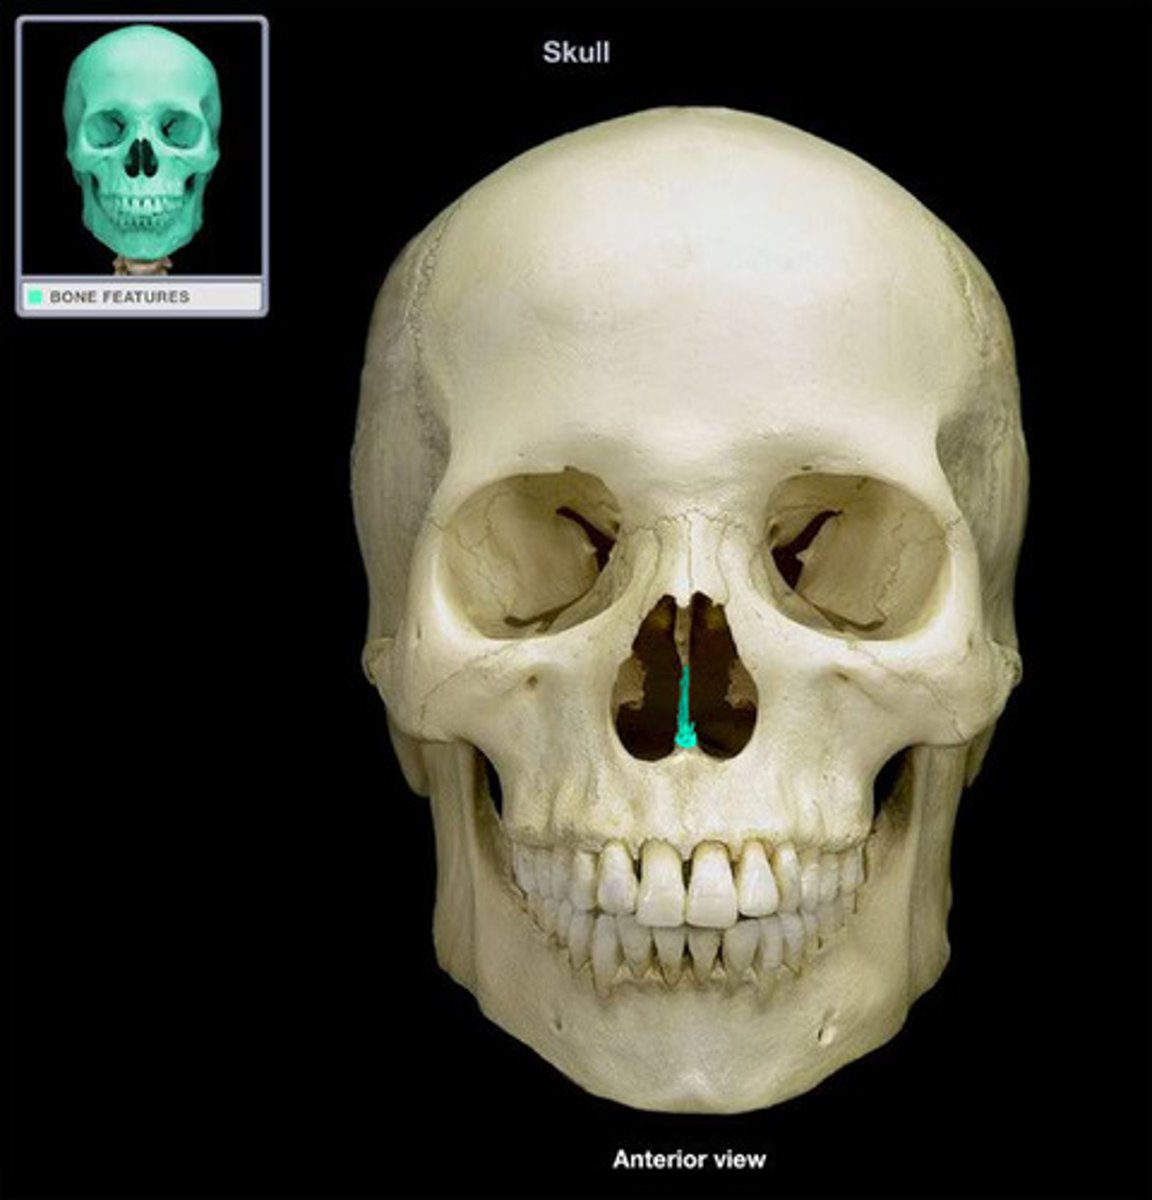

Vomer

Vomer